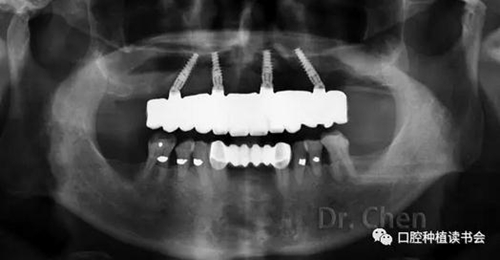

患者佩戴義齒后的口內(nèi)像和口外像(圖11、12),義齒外形、顏色、發(fā)音滿意,

曲斷片顯示所有氧化鋯接口與Multi-unit基臺之間完全就位,骨水平穩(wěn)定于植體頸部(圖13)。

患者佩戴永久修復體后半年復診,咀嚼功能及美觀、發(fā)音均滿意。骨水平穩(wěn)定,無機械及生物學并發(fā)癥。

13.jpg

▲ 永久修復后的曲斷片